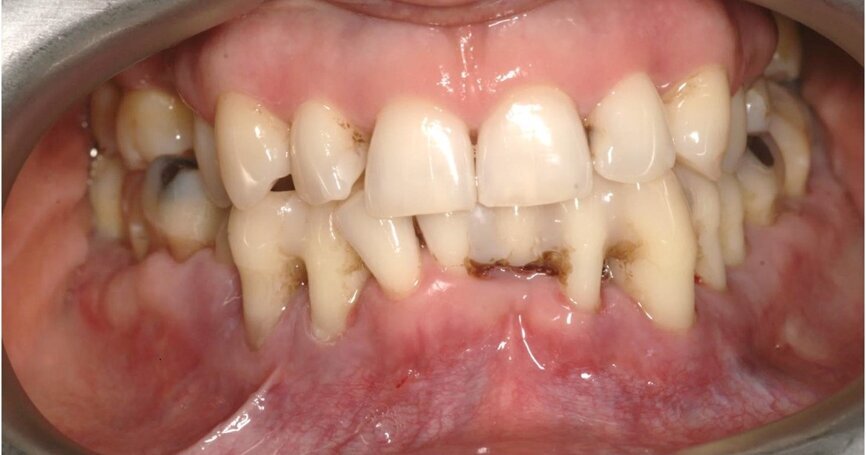

Badaniem wewnątrzustnym stwierdzono kieszenie o głębokości ponad 4 mm, wydzielinę ropną i krwawą, wskaźniki higieny wynosiły odpowiednio: API 25%, SBI 20%, wszystkie zęby w żuchwie wykazywały 3. stopień rozchwiania (Ryc. 1).

Wykonanie badania tomograficznego potwierdziło diagnozę o zaawansowanej nierokującej chorobie przyzębia (Ryc. 2). Po konsultacji została podjęta decyzja o ekstrakcji wszystkich zębów w żuchwie, natychmiastowym wprowadzeniu implantów z jednoczesną czasową odbudową protetyczna stałą mocowaną na wszczepionych implantach. Zlecono rutynowe badanie lekarskie i laboratoryjne.